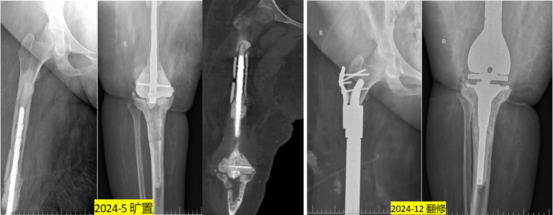

三、从手术实例看3D打印技术的“实战力”

因为古女士的情况复杂,手术难度大,医疗小组进行详细的病情分析和术前准备后,给古女士进行了右侧膝关节假体感染术后翻修术。整个手术历时200分钟,虽然手术过程中步骤不少,但凭借3D打印假体的精确适配等优势,术中操作顺利,患者生命体征平稳。术后在医护人员的照料下,古女士恢复得很好,很快就能活动了。